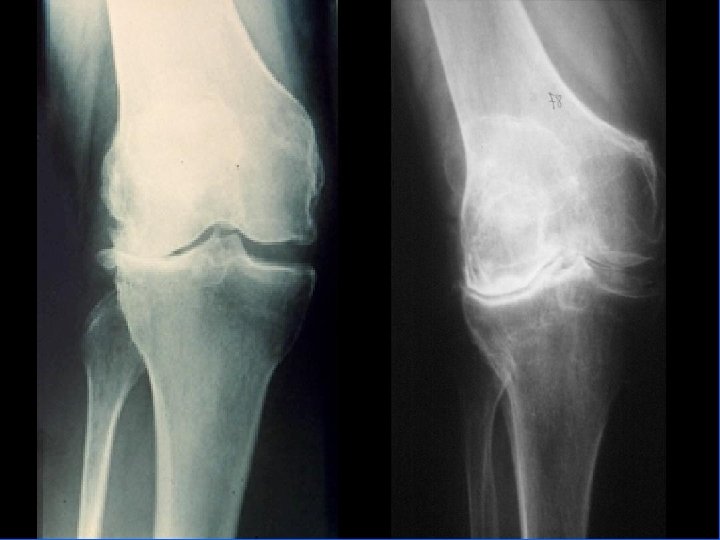

Arthrose fémoro-tibiale Iconographie • Radiographie : – Face en appui bipodal – Profil – Schuss (face en charge à 30° de flexion) pour compartiment post • Signes: – Pincement interligne – Ostéophytose – Ostéosclérose sous-chondrale avec géodes

Arthrose fémoro-tibiale Pronostic • Évolution très variable • Pas de facteurs pronostique bien individualisé mais semble que – obésité – antécédents traumatiques = Facteurs d’évolutivité